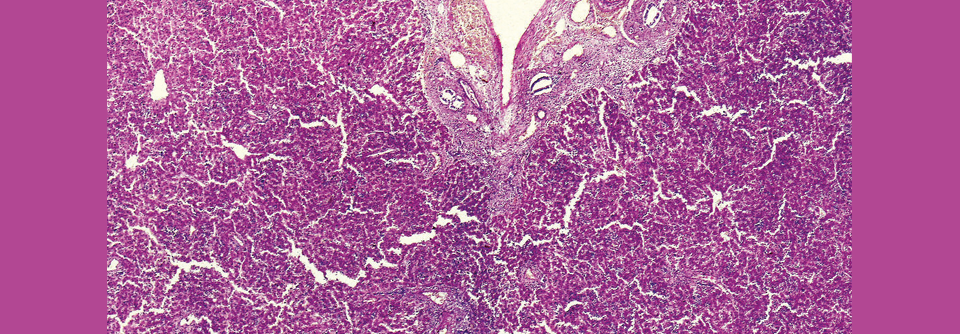

Über eine 47-jährige Patientin berichtete Prof. Dr. Dr. Matthias Dollinger, Medizinische Klinik I am Klinikum Landshut. Die kardial vorerkrankte Frau hatte erhöhte Transaminasen. Zur Abklärung erfolgte eine Leberbiopsie. Die Histologie war vereinbar mit einer Autoimmunhepatitis. Eine DILI erschien unwahrscheinlich: Fast alle ihre Medikamente nahm die Patientin bereits seit mehr als einem Jahr ein. Vor vier Monaten war zudem eine Antikoagulation mit Marcumar begonnen worden.

Besteht Unsicherheit, ob es sich um eine autoimmun bedingte oder medikamenteninduzierte Leberschädigung handelt, sollte man laut europäischen Leitlinien erst einmal anfangen, mit Hochdosissteroiden zu behandeln. Wenn die Transaminasen nach drei bis sechs Monaten abgefallen sind, kann man die Therapie wieder ausschleichen. „Ich biopsiere dann häufig auch noch mal“, erklärte Prof. Dollinger. „Wenn die Leber dann ausgeheilt ist, war es eine DILI, wenn nicht, ist es eine richtige, rezidivierende Autoimmunhepatitis.“